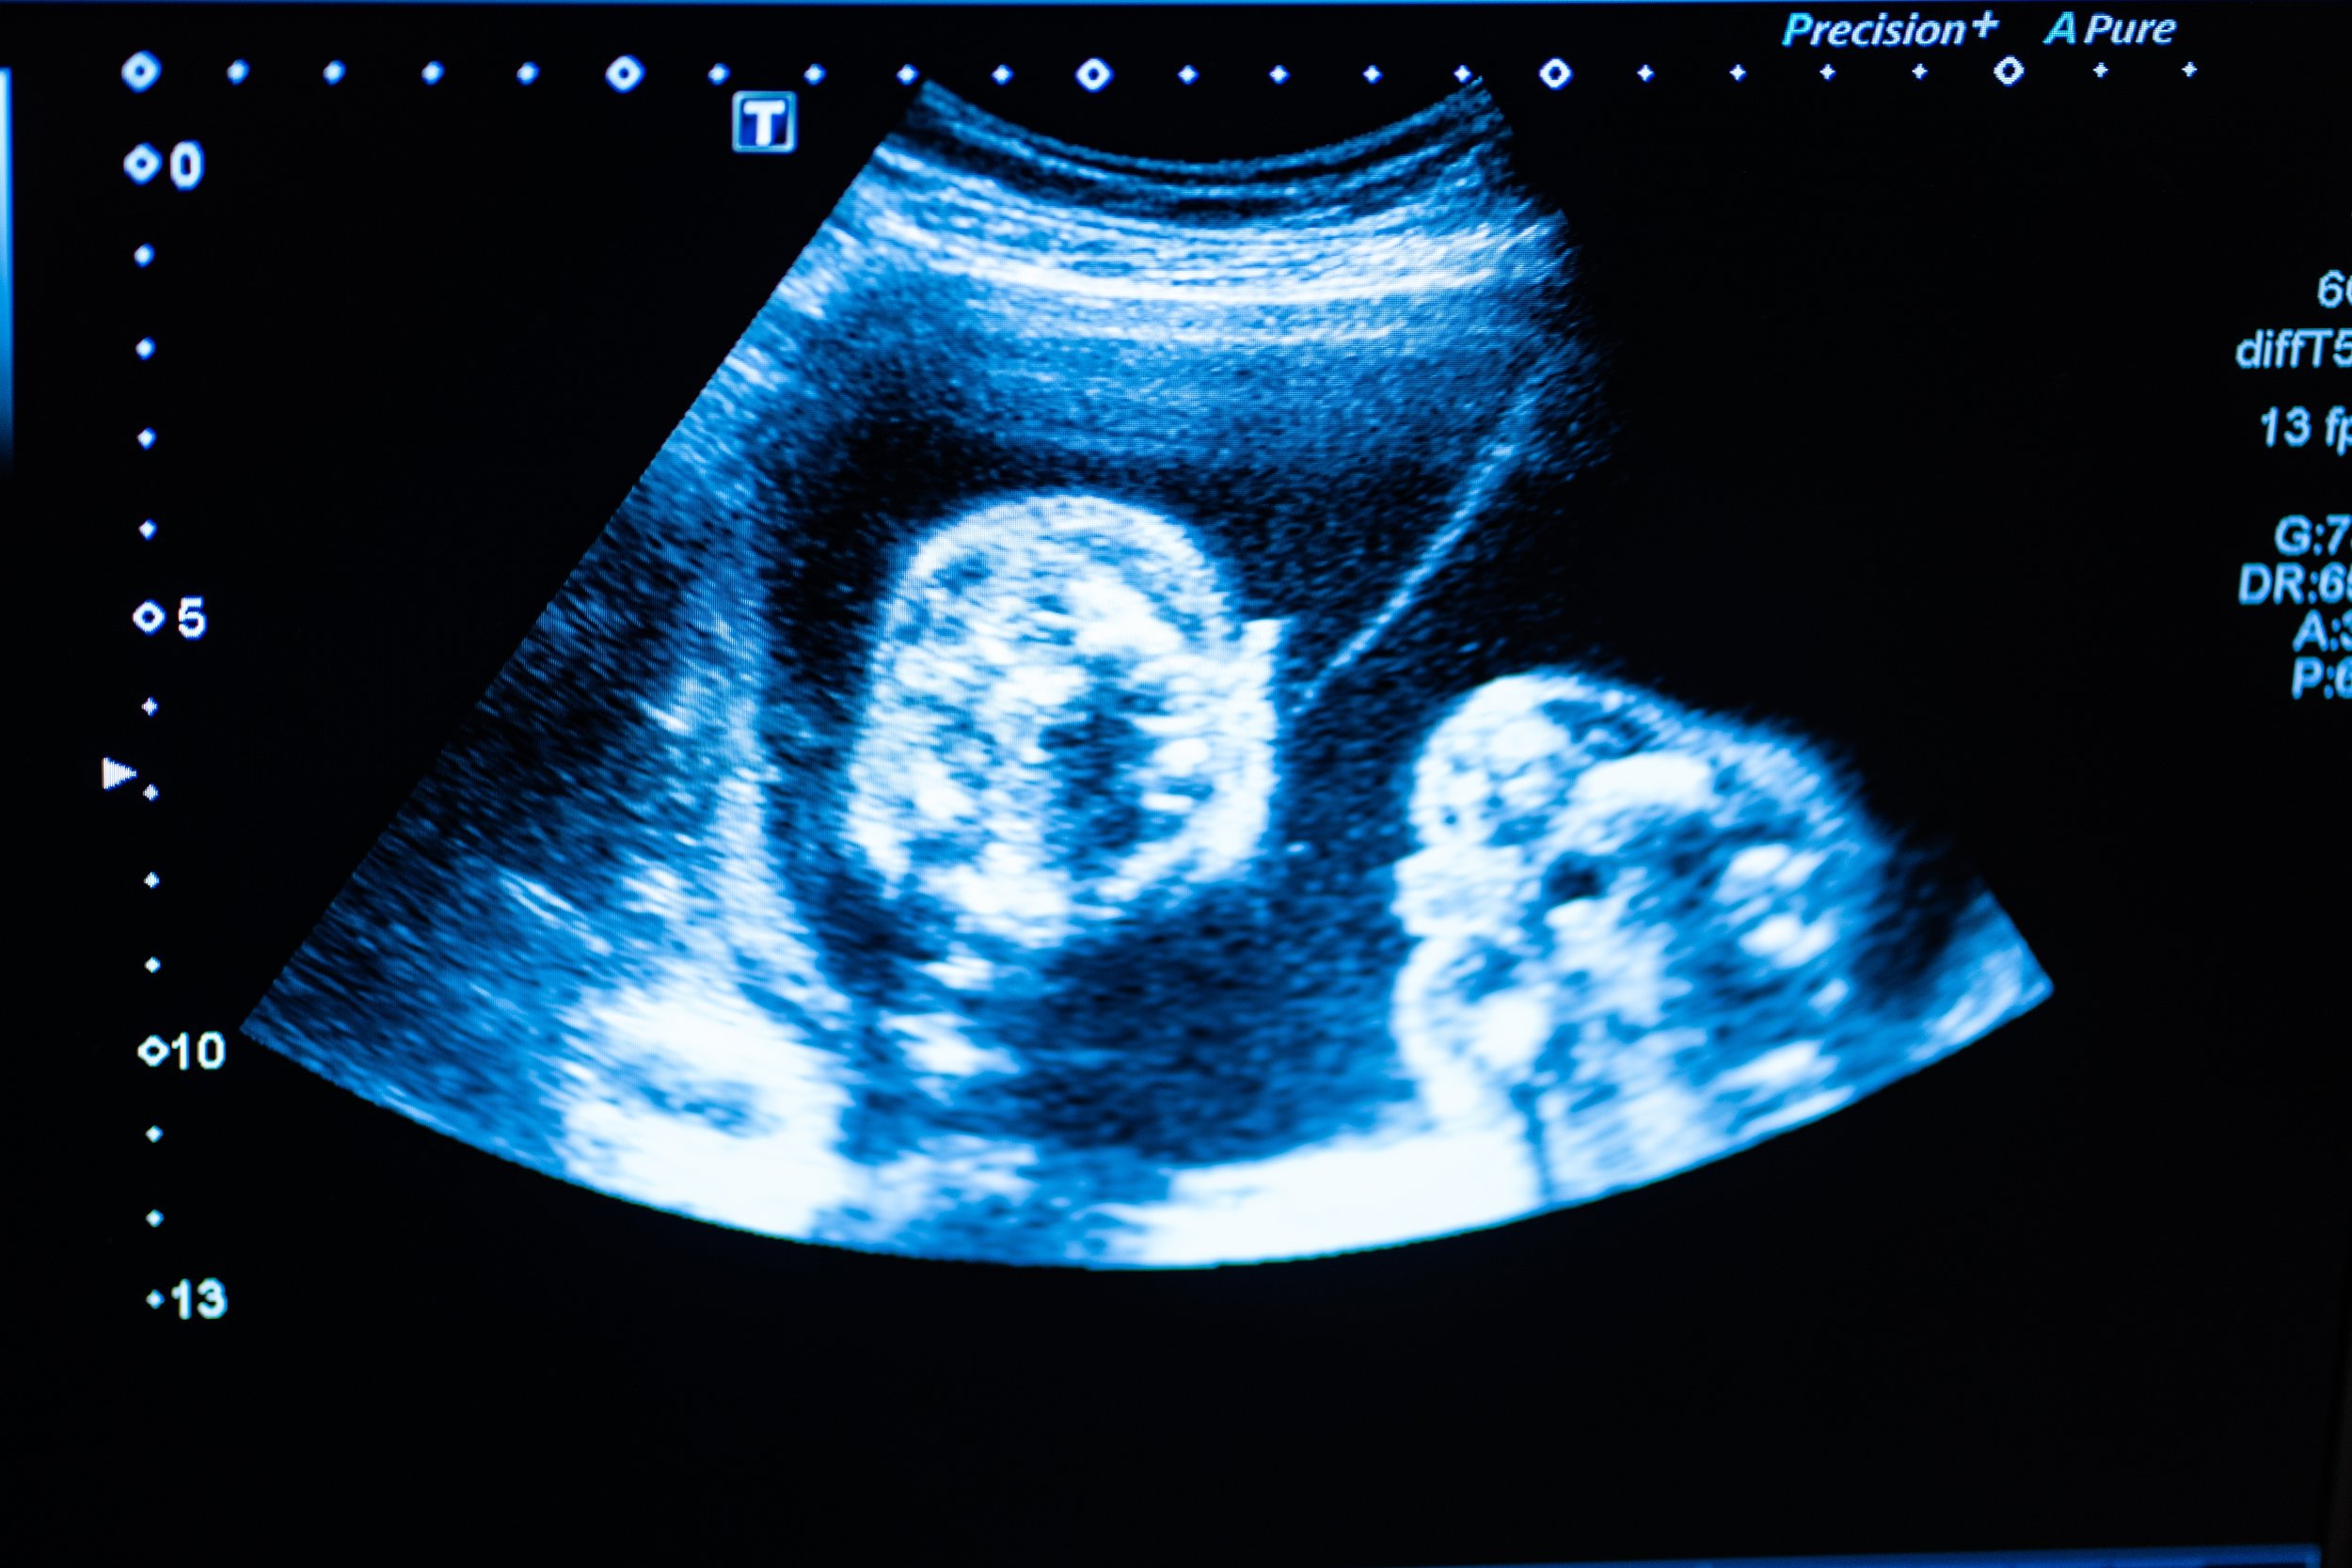

In Texas, access to reproductive healthcare is increasingly restricted. As of September 1, 2021, abortion became illegal once fetal cardiac activity can be detected, often around six weeks of pregnancy⁶.

The diagrams below map the relationships between healthcare access, policy restrictions, and maternal outcomes. By organizing these factors visually, systemic patterns are made more apparent and easier to see and discuss.